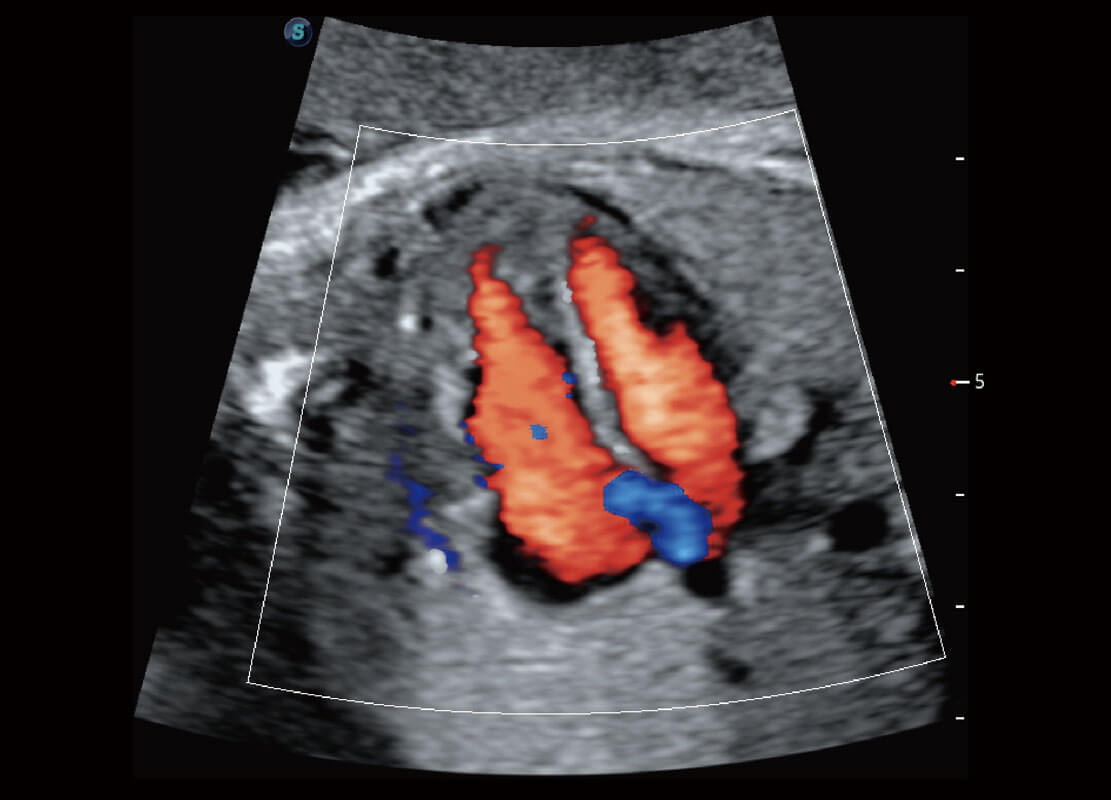

P60优异的图像质量搭载专科探头,在妇科基础疾病的诊断、卵泡生长的监测、输卵管通畅情况的判别等方面为您提供生殖应用方案。

腔内妇科-卵巢